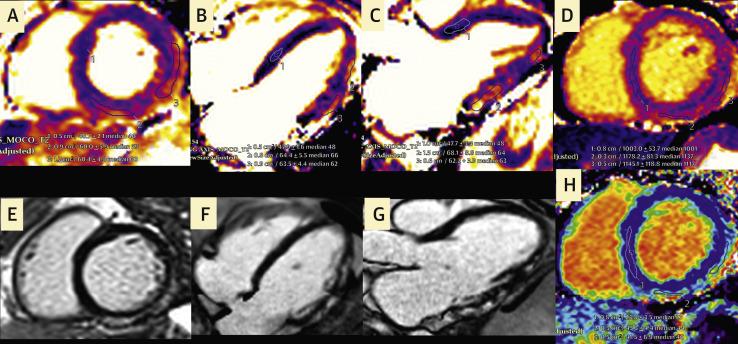

Possible Association Between COVID-19 Vaccine and Myocarditis: Clinical and CMR Findings.

JACC Cardiovasc Imaging. 2021 Sep;14(9):1856-1861. doi: 10.1016/j.jcmg.2021.06.002. Epub 2021 Jun 16.